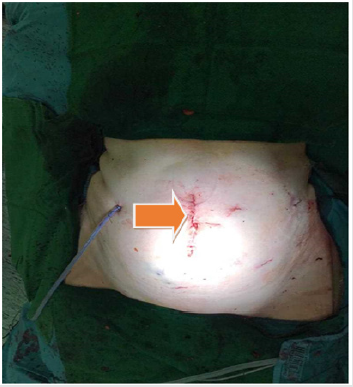

The removal of specimens took place in a fashion similar to conventional laparoscopy by using a small incision in the middle line (Figure 6). The final histopathological examination of both specimens showed a R0- resection (Figure 7). The duration of stay in the Intensive Care Unit (ICU) was one day and overall there were no signs of a disorder of renal or hepatic function or other postoperative complications. The patient recovered from this major surgical procedure and was discharged after eight days of an unremarkable postoperative course.

Figure 6: postoperative outcome after surgery and retrieval of both specimens through a small incision in the middle line (arrow).